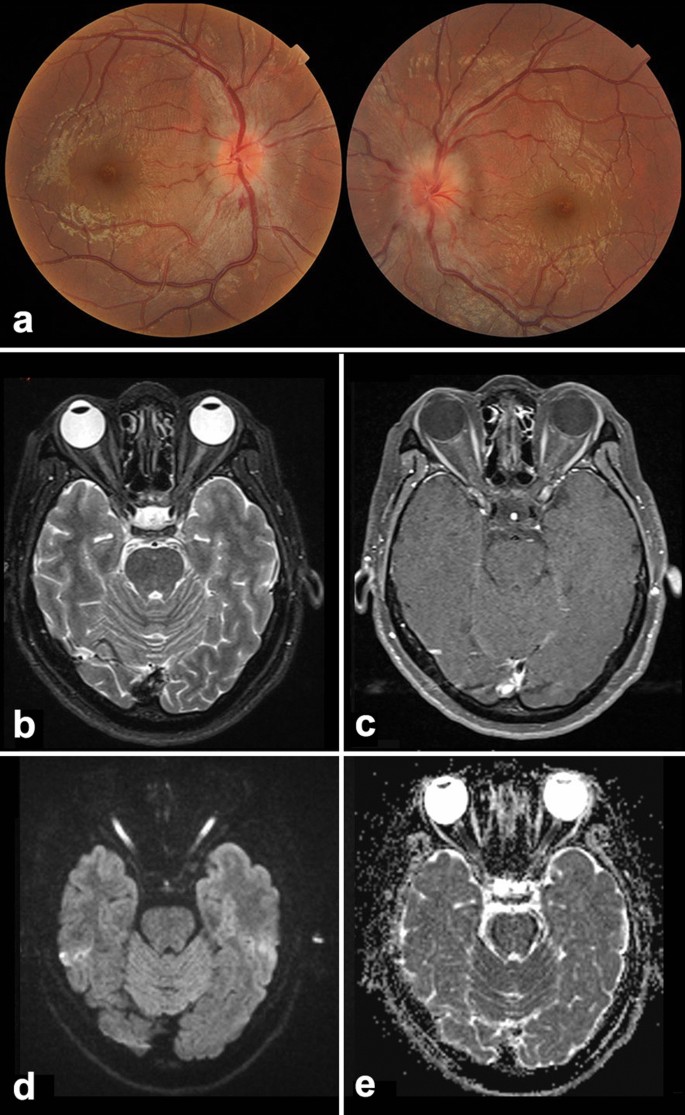

Our prospective 3-year study included a considerably large cohort of Chinese patients with ON. Surprisingly, > 20% of patients in our cohort tested positive for serum MOG-Abs and were characterized by a distinct set of clinical features, such as young-age onset, bilateral involvement, severe disc swelling, longitudinally extensive nerve and sheath enhancement in MRI imaging, and good recovery, albeit with a high relapse rate7,9,16. Since our cohort also included pediatric patients aged < 18 years old, the mean age of the MOG-ON group was much lower than that of the other studies and that reported for adult patients with MOG demyelinating disorders7,11,12. Some pediatric patients presented with fever, headache, and seizures before vision loss, without a definitive diagnosis; however, during the workup for acute ON, the MRI scan showed some subclinical demyelinating lesions in the brain and optic nerves, which was consistent with acute disseminated encephalomyelitis (ADEM) (Fig. 2a). Furthermore, ON could be viewed as a window to the brain17. It is easy for a neuro-ophthalmologist to diagnose MOG-associated disorders when the optic nerve is involved, regardless of the presence of previous brain lesions, which may be confusing for neurologists (Fig. 2b).

Patients who had a positive result for myelin oligodendrocyte glycoprotein antibodies presenting with brain lesion without diagnosis. (a, b) Images of a 12-year-old boy presenting with acute visual loss in the left eye for 10 days. One month ago, he experienced sudden loss of consciousness and a seizure. Fundoscopy (a) shows obvious edema of the optic disc, and brain and orbit magnetic resonance imaging (MRI) (b) shows enlarged and enhanced left optic nerve with brain lesions, indicating acute disseminated encephalomyelitis-like demyelinating disease, which was the probable cause for the seizure. (c, d) Images of a 30-year-old woman presenting with acute visual decrease in the right eye for 2 weeks. One month ago, she complained of weakness in her right body, while brain MRI showed a midbrain lesion, which recovered spontaneously. Fundoscopy (c) shows a severe swelling of the optic disc, and orbit MRI (d) shows extensive enhancement of the nerve.

Our study showed that the final BCVA of the patients with ON at the 3-year follow-up was favorable in the MOG-ON and seronegative-ON groups, despite the several recurrences observed in the MOG-ON group. Nearly 85% of eyes in the MOG-ON group and > 75% eyes in the seronegative-ON group recovered to > 20/25 visual acuity. In contrast, the BCVA was < 20/200 in more than one-third of the patients in the AQP4-ON group. There were also some exceptional cases in our cohort wherein patients with bilateral involvement and severe ON tested negative for both MOG-Abs and AQP4-Abs and had a very poor prognosis for visual recovery. Acute-stage orbit MRI in these patients showed hyperintensity on the diffusion-weighted image instead of optic nerve enhancement after intravenous gadolinium administration (Fig. 3). The exact etiology for MOG-ON remains unknown; however, we presume that some unknown infectious toxic processes or unknown antibodies attacking the optic nerve axons might be involved, rather than the current demyelinating mechanisms involved in seronegative-ON cases18,19.

A 20-year-old young man with acute profound bilateral visual loss, seronegative for myelin oligodendrocyte glycoprotein and aquaporin 4 antibodies. (a) The disc is swollen bilaterally with hemorrhage; (b–e) Orbit magnetic resonance imaging (MRI) at the acute stage showing mild hyperintensity of the optic nerves on T2-weighted imaging (WI) (b), no enhancement on T1WI after contrast (c); diffusion-weighted MRI (d) showing extreme hyperintensity of bilateral optic nerves with reduced apparent diffusion coefficient (e) value, indicating severe damage of the nerve. The best-corrected visual acuity at the 3-year follow up was 20/400 OU.